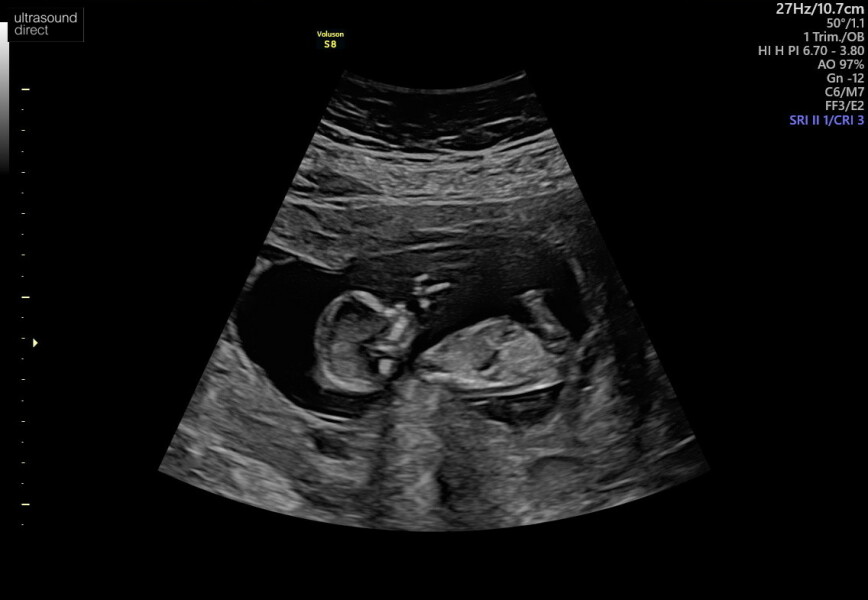

Hi everyone, I can not keep up with this thread 🤣 I hope everyone is okay, as my nhs scan isn’t booked until 13+6, I had a scan yesterday at 12+5 (private) and it’s lifted my anxiety so much seeing how much my baby has grown and seeing their heart beating away ♥️♥️♥️

Anyone else due July after a MC? 🌈

@Mamaoftwooo ahh this is amazing congratulations and what a lovely scan picture how nice ❤️ glad your feeling better too. I had my booking appointment last night which went ok just over one more week until my dating scan 🙏🏼🙏🏼🙏🏼got really bad heartburn which hoping that’s a good sign and legs have been achining in bed.

@Mamaoftwooo ah what a lovely photo, glad everything all went okay🥰